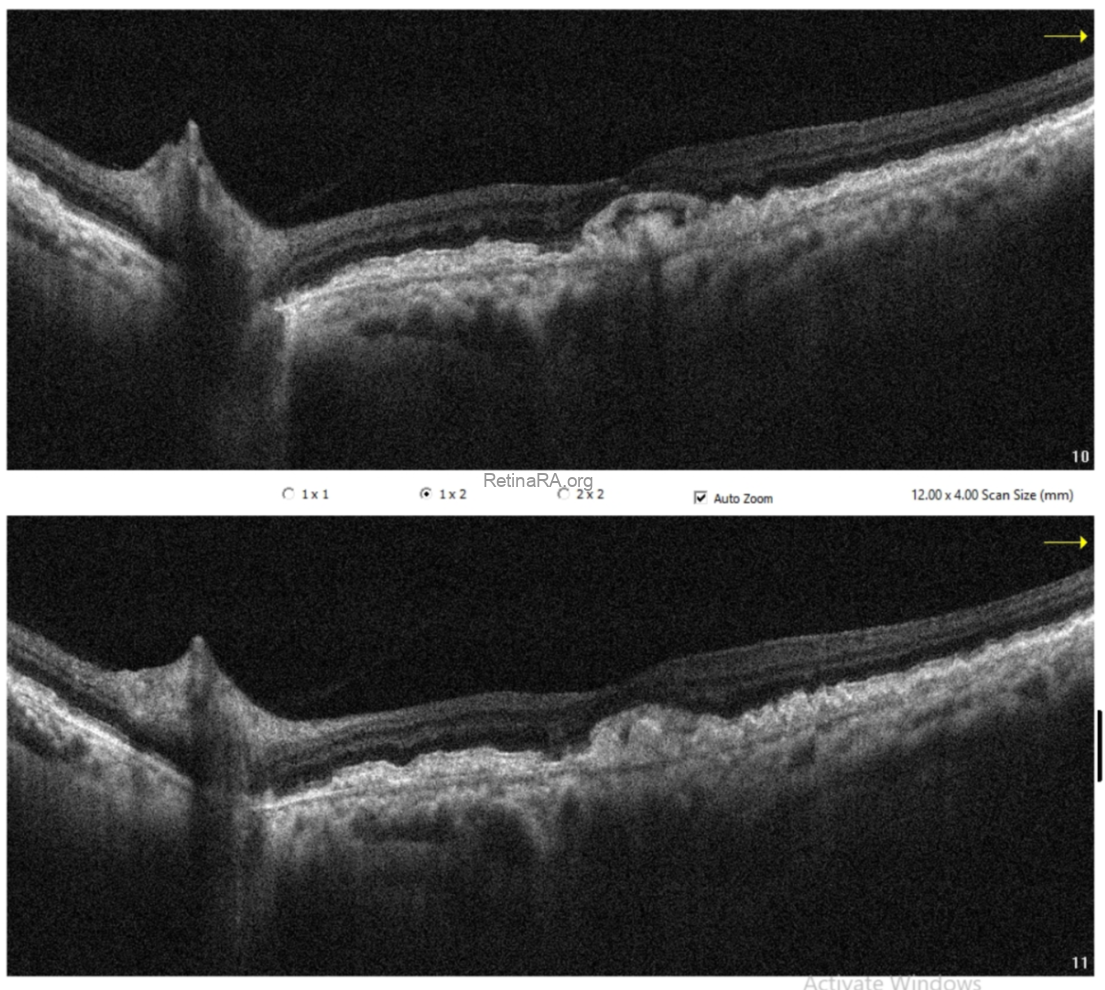

Optical coherence tomography (OCT) demonstrated extensive drusen-like deposits bilaterally, with areas of Bruch’s membrane thickening. In the right eye, there were vitreopapillary traction and an epiretinal membrane associated with a lamellar macular hole configuration, consistent with lamellar hole–associated epiretinal proliferation (LHEP). In the left eye, similarly dense deposits were observed, along with a subtle subfoveal subretinal fluid accumulation. Additionally, there appeared to be localized thickening at the level of the photoreceptor layers.

OCT angiography did not reveal any evidence of choroidal neovascularization. The subretinal fluid was therefore considered likely secondary to retinal pigment epithelium dysfunction.